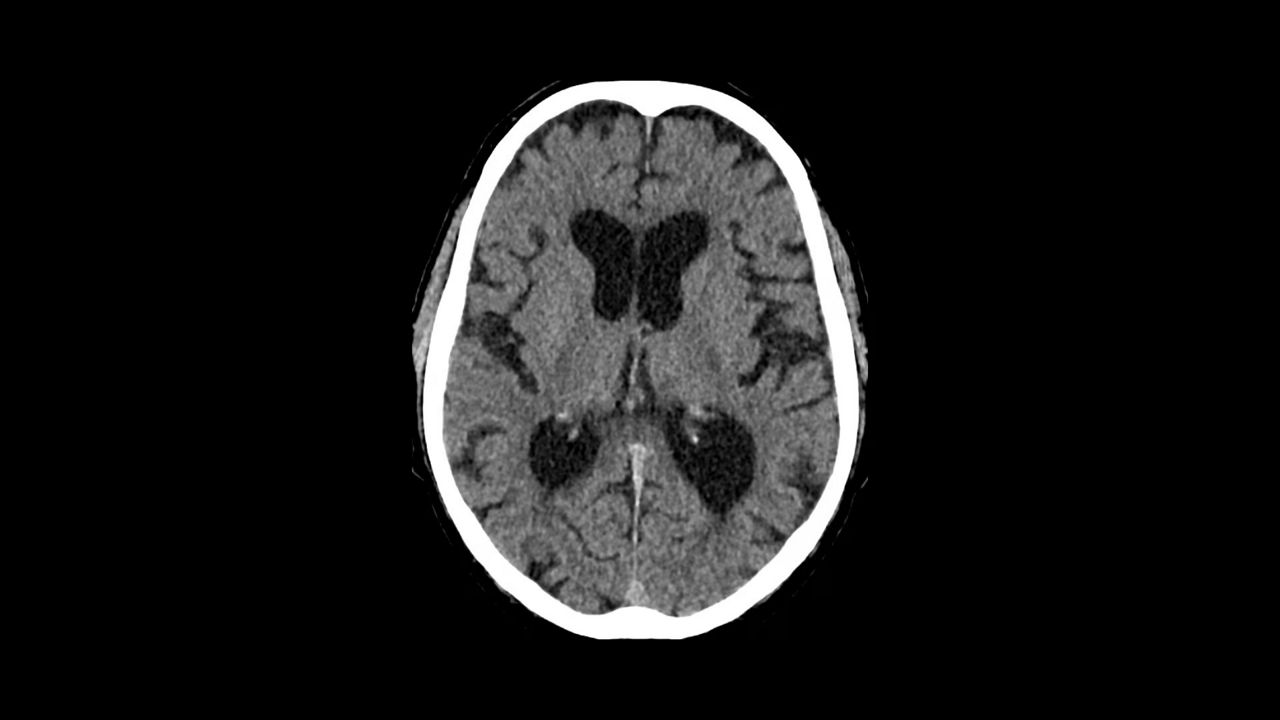

Simplify the Stroke CT workflow and the communication within the stroke team.

<p>FastStroke with StrokeSENS<sup>3</sup></p>

Learn more

<p>CT Perfusion 4D Neuro</p>

<p>Dynamic Shuttle</p>